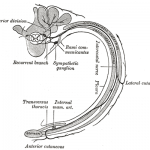

Auszug aus Wikipedia zu „Intercostal Nerv“:

Der Nervus intercostalis (dt. „Zwischenrippennerv“, auch Nervus subcostalis, „Unterrippennerv“) entspricht dem vorderen Ast (Ramus anterior) des jeweiligen Spinalnerven im Bereich der Brustwirbelsäule bzw. des Brustkorbes. Die Anzahl der Interkostalnerven einer Seite entspricht der Zahl der Rippenzwischenräume (Intercostalräume) – beim Menschen sind es also elf auf jeder Seite – bei zwölf Thorakalwirbeln/Rippenpaaren. (Der letzte, unterhalb der 12. Rippe laufende Nerv wird Nervus subcostalis genannt.) Sie versorgen motorisch die Zwischenrippen- und Bauchmuskulatur sowie die Haut im Bereich der Brust- und oberen Bauchwand. Sie verlaufen jeweils mit einer Arterie und einer Vene an der Unterkante der entsprechenden Rippe.

Der Nervus intercostalis (dt. „Zwischenrippennerv“, auch Nervus subcostalis, „Unterrippennerv“) entspricht dem vorderen Ast (Ramus anterior) des jeweiligen Spinalnerven im Bereich der Brustwirbelsäule bzw. des Brustkorbes. Die Anzahl der Interkostalnerven einer Seite entspricht der Zahl der Rippenzwischenräume (Intercostalräume) – beim Menschen sind es also elf auf jeder Seite – bei zwölf Thorakalwirbeln/Rippenpaaren. (Der letzte, unterhalb der 12. Rippe laufende Nerv wird Nervus subcostalis genannt.) Sie versorgen motorisch die Zwischenrippen- und Bauchmuskulatur sowie die Haut im Bereich der Brust- und oberen Bauchwand. Sie verlaufen jeweils mit einer Arterie und einer Vene an der Unterkante der entsprechenden Rippe.